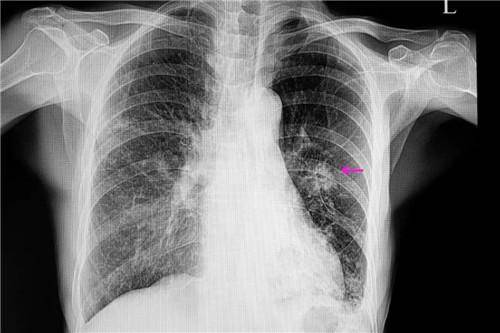

肺结节影是指患者在做胸部平片的检查或者胸部CT、磁共振检查的时候,发现肺部有阴影或者肿物,称之为肺结节影。肺结节影的原因还是比较多的,最常见的原因是因为感染性因素,如果是普通的感染,会伴有发高烧的情况,还会有咳嗽和咳痰,需要根据感染的类型选择抗生素、抗病毒或者支原体的药物治疗。另外一种肺结节影有可能是良性肿瘤或者恶性肿瘤,需要及早的进行手术切除。

如果肺结节影的边界较清,直径小于3mm,通常来说并不严重。如果通过结节的体积过大,直径超过3cm,需要考虑是否为肺部恶性肿瘤,多数比较严重。